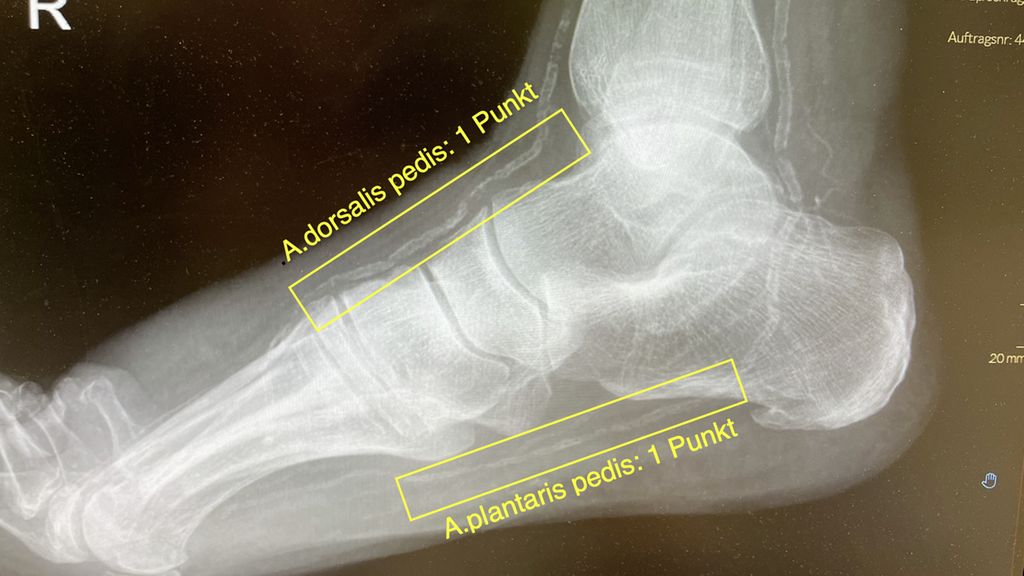

Ferraresi und seine Kollegen haben einen sehr einfach zu erhebenden MAC-Score entwickelt, der dem oben beschriebenen SAD-Score frappierend ähnelt, sowohl in der Erfassung der Schwere der Erkrankung als auch in der davon abzuleitenden Prognose.2,3 Dafür benötigt es lediglich konventionelle Röntgenaufnahmen des Fußes dorsoplantar und seitlich. Es werden 5 Gefäße beurteilt mit der einfachen Frage, ob sie sichtbar sind: und zwar die A.dorsalis pedis und die plantare Arterie im seitlichen Bild und die intermetatarsale Arterie zwischen 1. und 2. Strahl im dorsoplantaren Bild. Wenn diese jeweils auf 2cm Länge verkalkt sind, gibt es dafür jeweils einen Punkt. Es folgen noch eine digitale Arterie am Großzeh (medial oder lateral) und eine beliebige digitale Arterie an den anderen kleinen Zehen – wenn diese auf jeweils 1cm Länge verkalkt zur Darstellung kommen, so gibt es auch dafür je einen Punkt. Die Punkte werde addiert (Abb. 1):

-

0–1 Punkt: MAC-Score 0 (keine MAC)

2–3 Punkte:MAC-Score 1 (moderat)

4–5 Punkte: MAC-Score 2 (schwer)